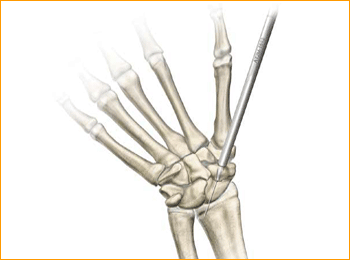

2. Guide Wire Insertion

Pass the guide wire through the needle and drill it across the fracture, continually checking the direction on the image intensifier and correcting as necessary, aiming for the radial aspect of the proximal pole. It is extremely important not to bend the guide wire and any adjustments in direction should be made using the needle as a guide rather than attempting to alter the line of the guide wire alone.

Dorsal Scaphoid Technique for 2.5 mm, 3 mm, 3.5 mm and 4 mm Headless Compression screws.

1. APPROACH AND NEEDLE INSERTION

The entry point in the proximal pole is at the tip of the scaphoid immediately adjacent to the scapholunate ligament. This can be located either using an arthroscopy or mini open dorsal approach between the third and fourth extensor compartments. Whichever approach is employed, it is essential to ensure that the guide wire does not transfix an extensor tendon.

Having established the entry point, introduce the appropriate guide wire aiming for the base of the thumb and check the position on the fluoroscope. Aim to place the leading edge of the guide wire in the subchondral surface of the distal pole of the scaphoid. Confirm the wire placement and depth under imaging.